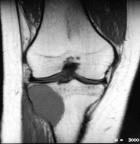

22 year old female with two month history of right knee pain

Zoom image: Radiological image Radiological image.